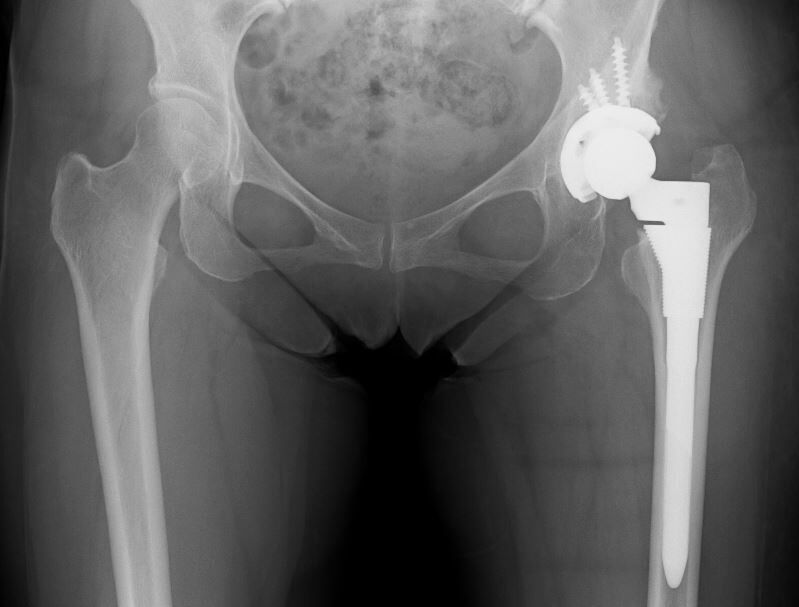

大腿骨にも過大前捻があり、関節不安定性がどうなるのか予測できなかったため、S-ROM-Aでこちらも20度減捻しました。

寛骨臼、大腿骨頚部とも大幅に角度調整したのですが、幸いにも易脱臼性はありませんでした。こういう症例は疲れますね...。